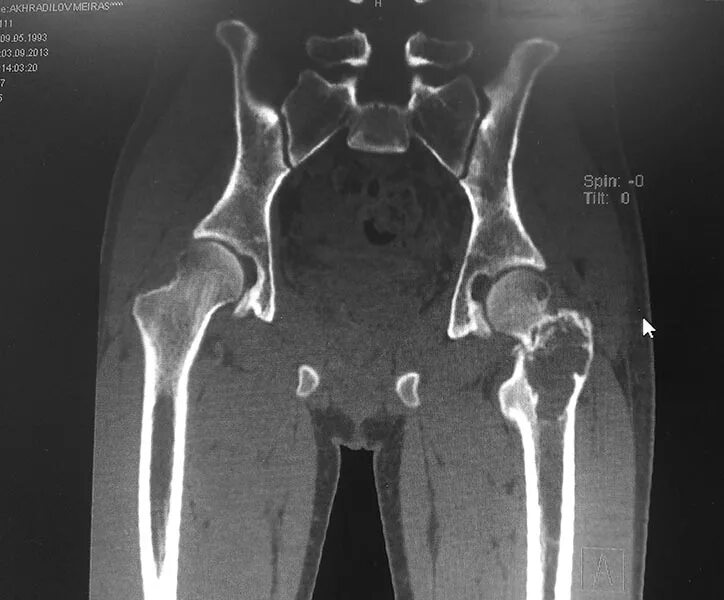

Кт суставов что показывает